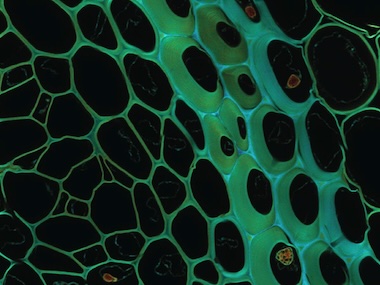

A project at the Italian Institute of Technology (IIT) has developed a method able to carry out simultaneous super-resolution imaging and optical sectioning in laser scanning microscopy.

Described in Nature Photonics, the technique allows scientists to see and photograph biological samples in all their complexity, said the team, obtaining clear and detailed images.

The study, from IIT's Molecular Microscopy and Spectroscopy group and funded within the European BrightEyes research project, was designed to address a specific issue: obtaining extremely sharp and detailed images of thick and complex biological samples.

The team developed a method for taking single-plane image data and reconstructing super-resolution optical sectioning, naming the technique super-resolution sectioning image scanning microscopy (ISM), or s2ISM.

In ISM a confocal laser scanning microscopy approach is combined with a detector array, which inherently encodes axial information within its imaging; but the complexity involved in recovering that axial data has been considerable. The IIT approach involved a conceptual change in how the ISM operation was framed by the researchers, who treated it as an exercise in structured illumination.

IIT designed an instrument in which a small array of sensors captures both the light at the point where it hits a tissue sample, and the way the light then spreads within that sample. Once this information is recorded, a reconstruction algorithm identifies the path of the light through the sample, as a way to produce sharper and better-sectioned images without losing signal quality.

"The optical microscope used is equipped with an array of SPAD (single-photon avalanche diode) detectors, capable of detecting the arrival of individual photons with very high spatial and temporal precision," said Alessandro Zunino from IIT.

"This characteristic not only improves the resolution and optical sectioning, but also enables advanced techniques such as fluorescence lifetime imaging, which are fundamental to explore molecular dynamics in living tissues and to provide functional as well as structural information."

Trials applying the s2ISM method to cell cultures and zebrafish embryos confirmed that it could outperform conventional image reconstruction techniques, and could be extended to any laser scanning microscopy technique.

"Potential applications are numerous: from studying brain tissue, tumors, organoids, and other complex biological systems, to direct observation of cellular life to understand disease progression," commented IIT. "In the pharmaceutical field, the technique could be used to visualize in real time how drugs interact with living biological tissues, speeding up and enhancing the accuracy of the discovery of new treatments and therapies."